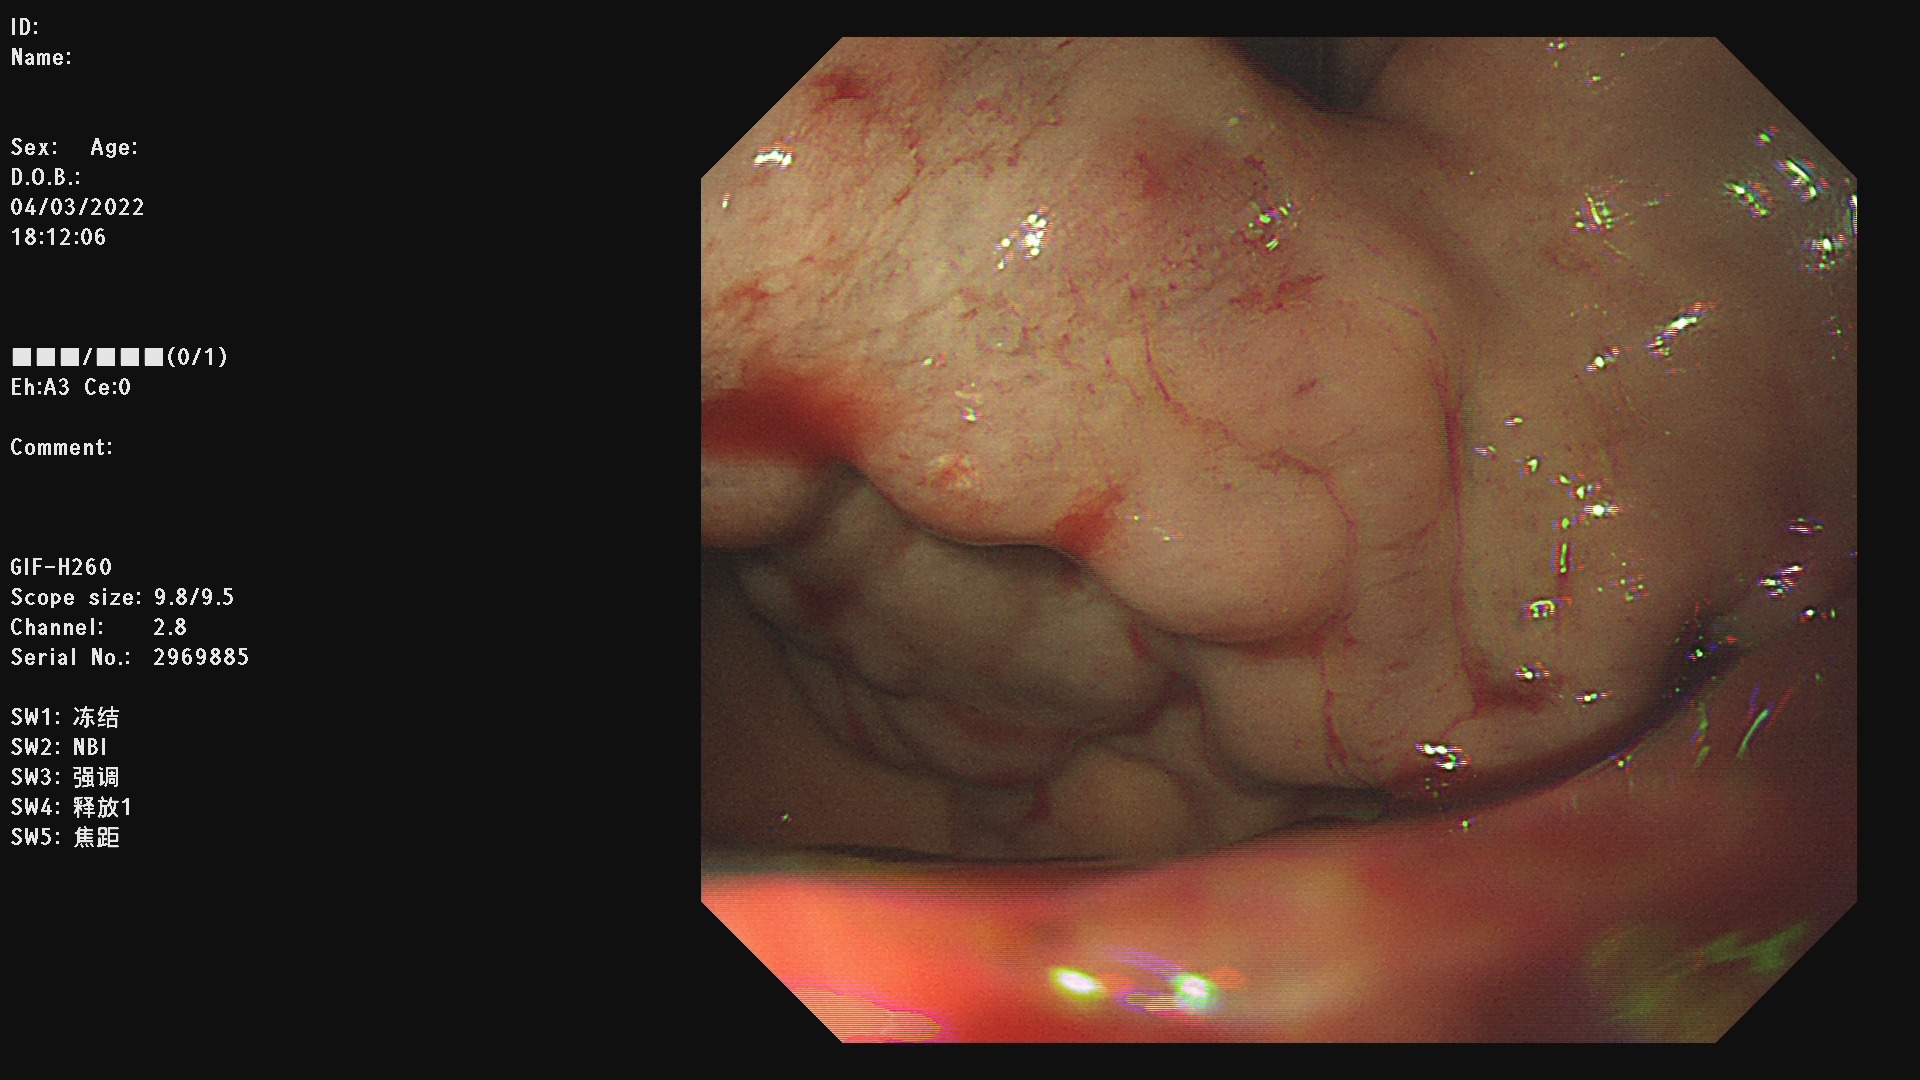

例二: